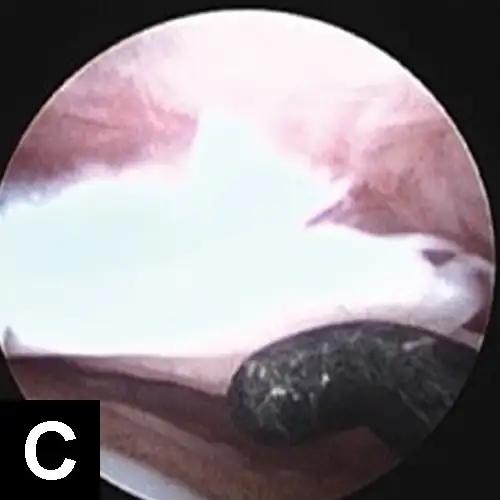

Large-breed dogs are most commonly affected, usually presenting with unilateral or bilateral forelimb lameness between 4 and 8 months of age. Muscle atrophy and pain during shoulder manipulation may be found in affected dogs. Diagnosis is based on clinical signs and radiographic visualization of flattening of the caudal aspect of the humeral head (Figure 10A). Positive-contrast arthrography may help in the diagnosis when radiographs are unclear (Figure 10B). Advanced imaging (eg, CT, MRI) can be helpful in elusive cases.Surgical or arthroscopic removal of the cartilage flap with debridement of the subchondral bone often leads to an excellent prognosis (Figure 10C).